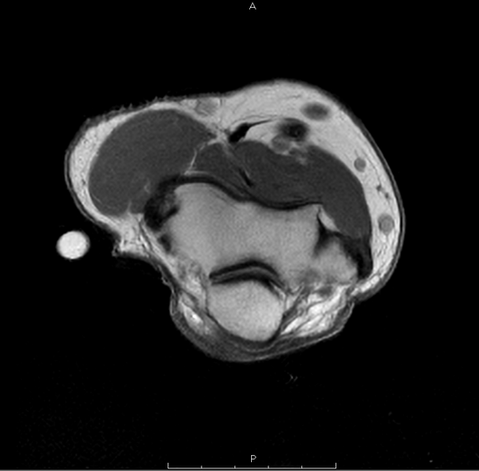

Real-World Impact: AI-Optimized Scan Times

Recent clinical implementation of SwiftMR™ at Stand-Up MRI has led to significant time savings across multiple scan types: